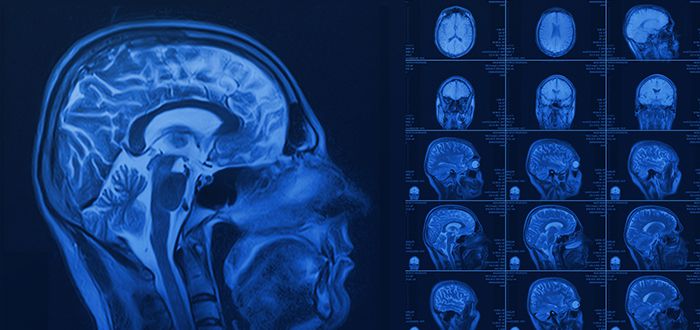

داخل جمجمتنا،يوجد شبكة طرق سريعة معقدة من الشرايين والأوعية الدموية التي تزاد دماغنا بالدم الغني بالأكسجين و لكن في بعض الحالات النادرة، يحدث خلل في تكوين هذه الشبكة، فتتحول إلى تشابك غير طبيعي من الأوعية يسمى "التشوه الشرياني الوريدي في الدماغ" أو ما يعرف بالتحالف الوعائي. يقول الدكتور محمد عطية استشاري أمراض المخ والأعصاب أن التشوه الشريانى الوريدى فى الدماغ  هو تشوه خلقي يشبه "متاهة" من الأوعية المتشابكة التي تربط الشرايين  بالأوردة دون وجود الشعيرات الدموية الوسيطة، مما يخلق تدفقاً دموياً سريعاً و عنيفاً و ضعفاً في جدار هذه الأوعية و هذا الضعف يجعلها قنبلة موقوتة، قابلة للتمزق في أي لحظة مسببة نزيفاً دماغياً قد يكون مميتاً. ويؤكد عطية  على أن يكمن الخطر الأكبر في أن الكثير من المرضى يعيشون سنوات دون أي أعراض إلى أن يحدث التمزق فجأة و قد تظهر على بعض المرضى أعراض تحذيرية مثل نوبات الصداع الشديدة والمتكررة، نوبات الصرع أو ضعف في أحد الأطراف. وأشار إلى أن  التشخيص يتم عن طريق التصوير بالأشعة المقطعية أوالرنين المغناطيسي للدماغ و يعتمد العلاج على حجم وموقع التشوه وعمر المريض وحالته الصحية ويتراوح بين المراقبة الدقيقة إذا كان التشوه صغيراً وغير عرضي أو اللجوء إلى طرق علاجية متقدمة مثل القسطرة العلاجية  عن طريق حقن مواد لسد الأوعية أو الجراحة الميكروسكوبية لإزالة التشوه أو العلاج الإشعاعي المركز لتدميره تدريجياً و الاكتشاف والعلاج المبكران هما المفتاح لمنع حدوث نزيف دماغي .